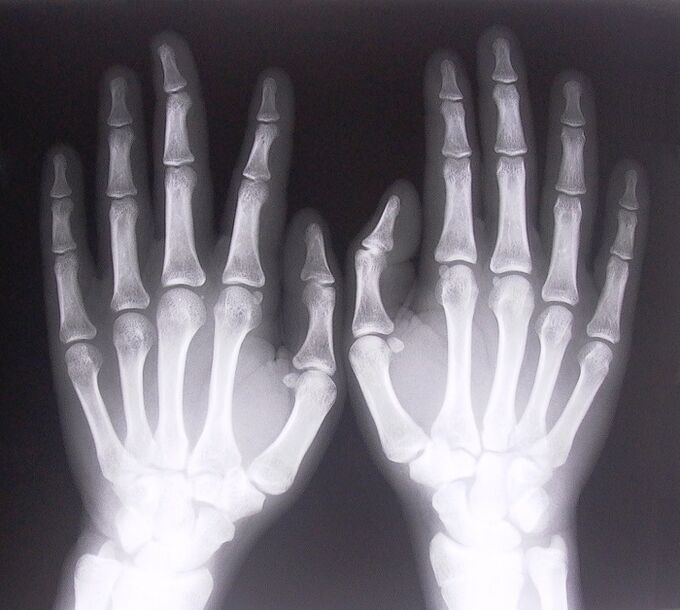

- Stenotic ligamentitis.In order to determine the cause of the disease, it is necessary to undergo an X-ray examination.The symptoms are typical: painful movement of the hand, a loop of the clenched palm.In addition, clicks are usually heard during extension.

To start treating pain in the joints of the fingers, you need to correctly determine what disease caused them.To determine what type of disease affects a person who experiences pain in the joints when bending their arms, doctors recommend undergoing the following procedures:

- Take x-rays.